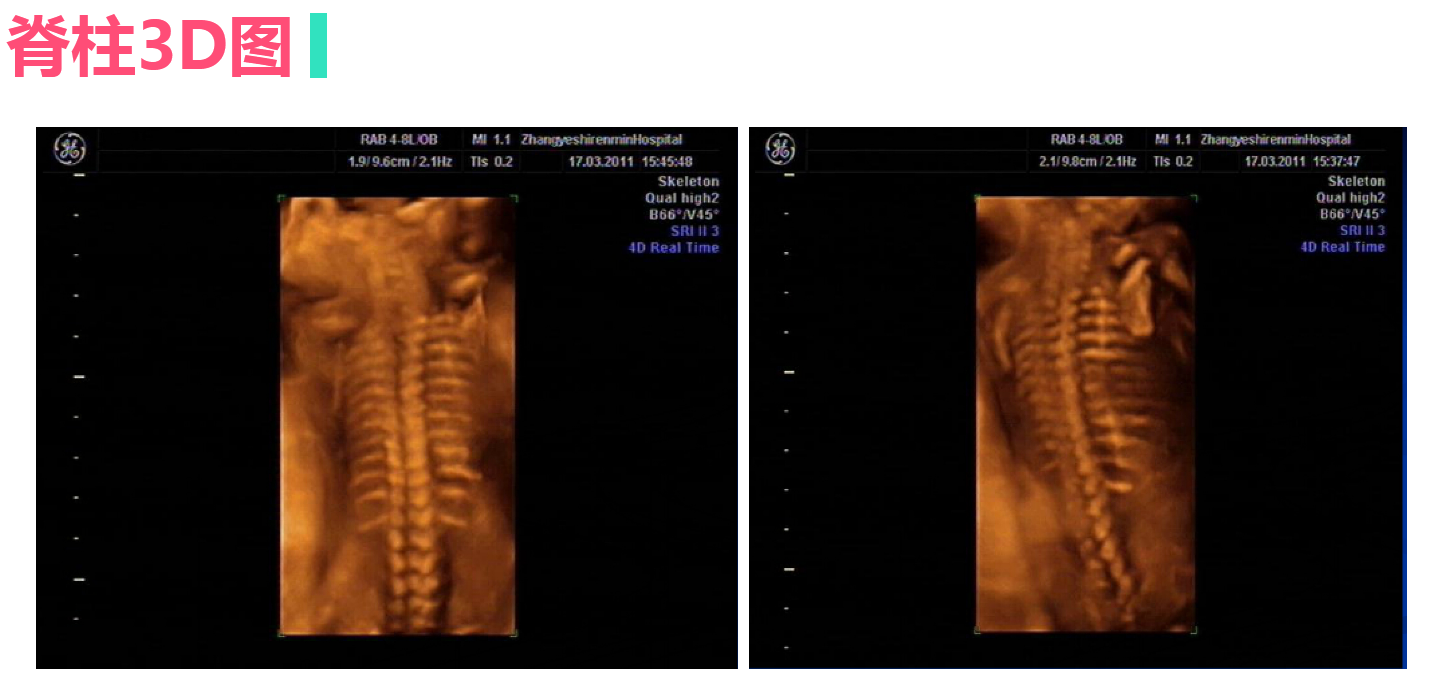

正常中晚期妊娠声像图

• 4.4 异常妊娠声像图